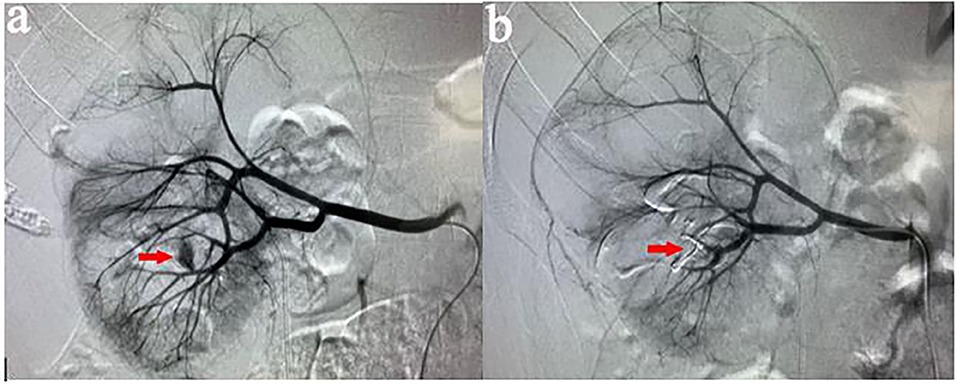

Renal angio-embolization is a minimally invasive interventional radiology procedure used to block abnormal or bleeding blood vessels in the kidney. It is performed to stop internal bleeding, control tumors, or treat vascular malformations without open surgery.

The procedure involves using a catheter to deliver special materials (like coils, glue, or particles) into the renal artery to selectively block the targeted blood flow.

• Using real-time imaging, the catheter is guided to the affected renal vessel

• Embolic material is injected to block blood supply to the bleeding or abnormal area

• Coils – tiny metal spirals that create a physical blockage